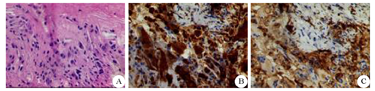

患者男性,32岁,务农,未婚。以"双下肢无力并行走不稳3年"为主诉于2018年5月2日收入我科。3年前无明显诱因逐渐出现双下肢无力并行走不稳,持续性存在,休息后不能缓解,不影响日常生活,无晨轻暮重、感觉异常、肌肉萎缩等。双上肢无明显异常。自觉上述症状逐渐加重,逐渐出现步态异常,易跌倒,方向不定。既往史、个人史无特殊。父母均为汉族,体健,非近亲结婚,1兄、1姐及其兄姐双方的子女均体健,余家族史亦无特殊。体检:生命体征均在正常范围内。体型偏小、瘦弱,皮肤黏膜无色素沉着。认知粗测正常,精神状态良好。两侧肌肉对称,未见明显萎缩、肥大;双上肢肌力5级,肌张力正常,双侧肱二头肌、肱三头肌、桡骨膜反射均亢进(++++),双侧Hoffmann征、Rossolimo征均阳性。双下肢肌力4级,肌张力增高,双侧踝阵挛阳性,双侧膝腱反射、跟腱反射均亢进(++++),双侧Babinski征及其等位征均阳性。腹壁反射亢进(+++)。双侧跟-膝-胫试验欠稳准,闭目难立征阳性,剪刀步态。深、浅、复合感觉正常。脑膜刺激征阴性。双侧跟腱可视、触及对称性增粗,余肌腱未触及明显增粗。血同型半胱氨酸27.14 μmol/L(正常值范围为0~15 μmol/L)。头颅3.0 T MRI平扫提示双侧小脑齿状核异常信号(图1A)。全脊椎1.5 T MRI平扫提示颈、胸、腰椎退行性病变;腰1~5椎体多发异常信号,考虑脂肪岛;骶管囊肿(图1B)。胸部CT提示右肺中叶小结节及条索状病灶。腹部脏器彩超提示胆囊壁毛糙,附壁可见数个点状强回声。双侧跟腱彩超提示双侧跟腱弥漫性增粗,回声减低,腱纤维回声紊乱,后方回声明显衰减,内可见少许彩色血流信号。右侧跟腱活检可见炎细胞及大量组织细胞浸润,大量胆固醇结晶,符合跟腱黄色瘤病理特征(图2)。对CYP27A1基因的外显子编码区进行一代测序,结果提示2个位点的突变:c.1263+1G>A和c.1420C>T (Arg474Trp)(图3)。进一步检查提示其父亲存在c.1263+ 1G>A突变,母亲存在c.1420C>T突变。

Imaging data of the patient

A:头颅MRI平扫;B:脊椎MRI平扫,显示腰椎椎体多发脂肪岛形成